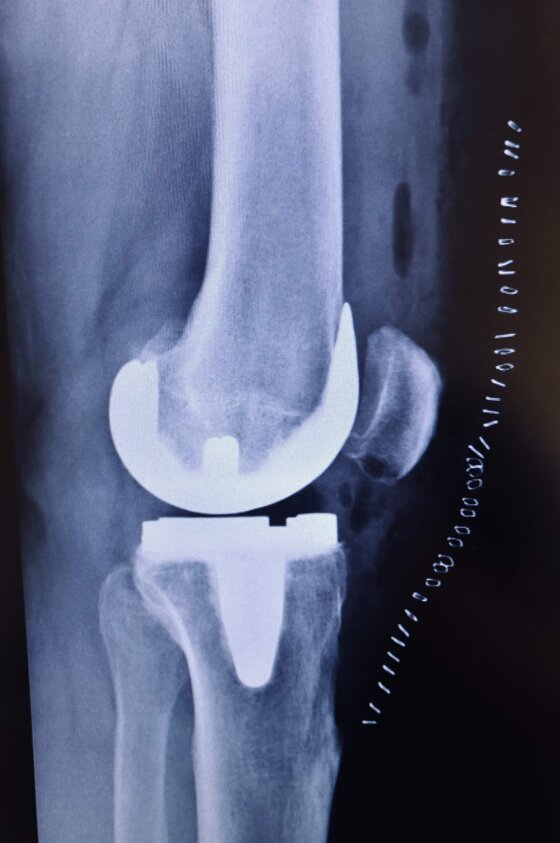

A sinistra radiografie pre-operatorie il AP e LL che evidenziano una grave gonartrosi diffusa con presenza di osteofiti periarticolari e deformità associata (ginocchio varo).

A destra radiografia post-operatoria in AP e LL di intervento chirurgico di artroprotesi di ginocchio cementata, unico trattamento possibile con pz che presentava dolore continuo e zoppia. Ho utilizzato una protesi con risparmio del legamento crociato posteriore (CR) chiamata Persona proprio perché altamente anatomica, cioè molto rispettosa dell’anatomia del ginocchio del singolo paziente. La paziente presentava un sovrappeso per cui ho optato per una componente protesica tibiale con un fittone più lungo proprio per avere più resistenza